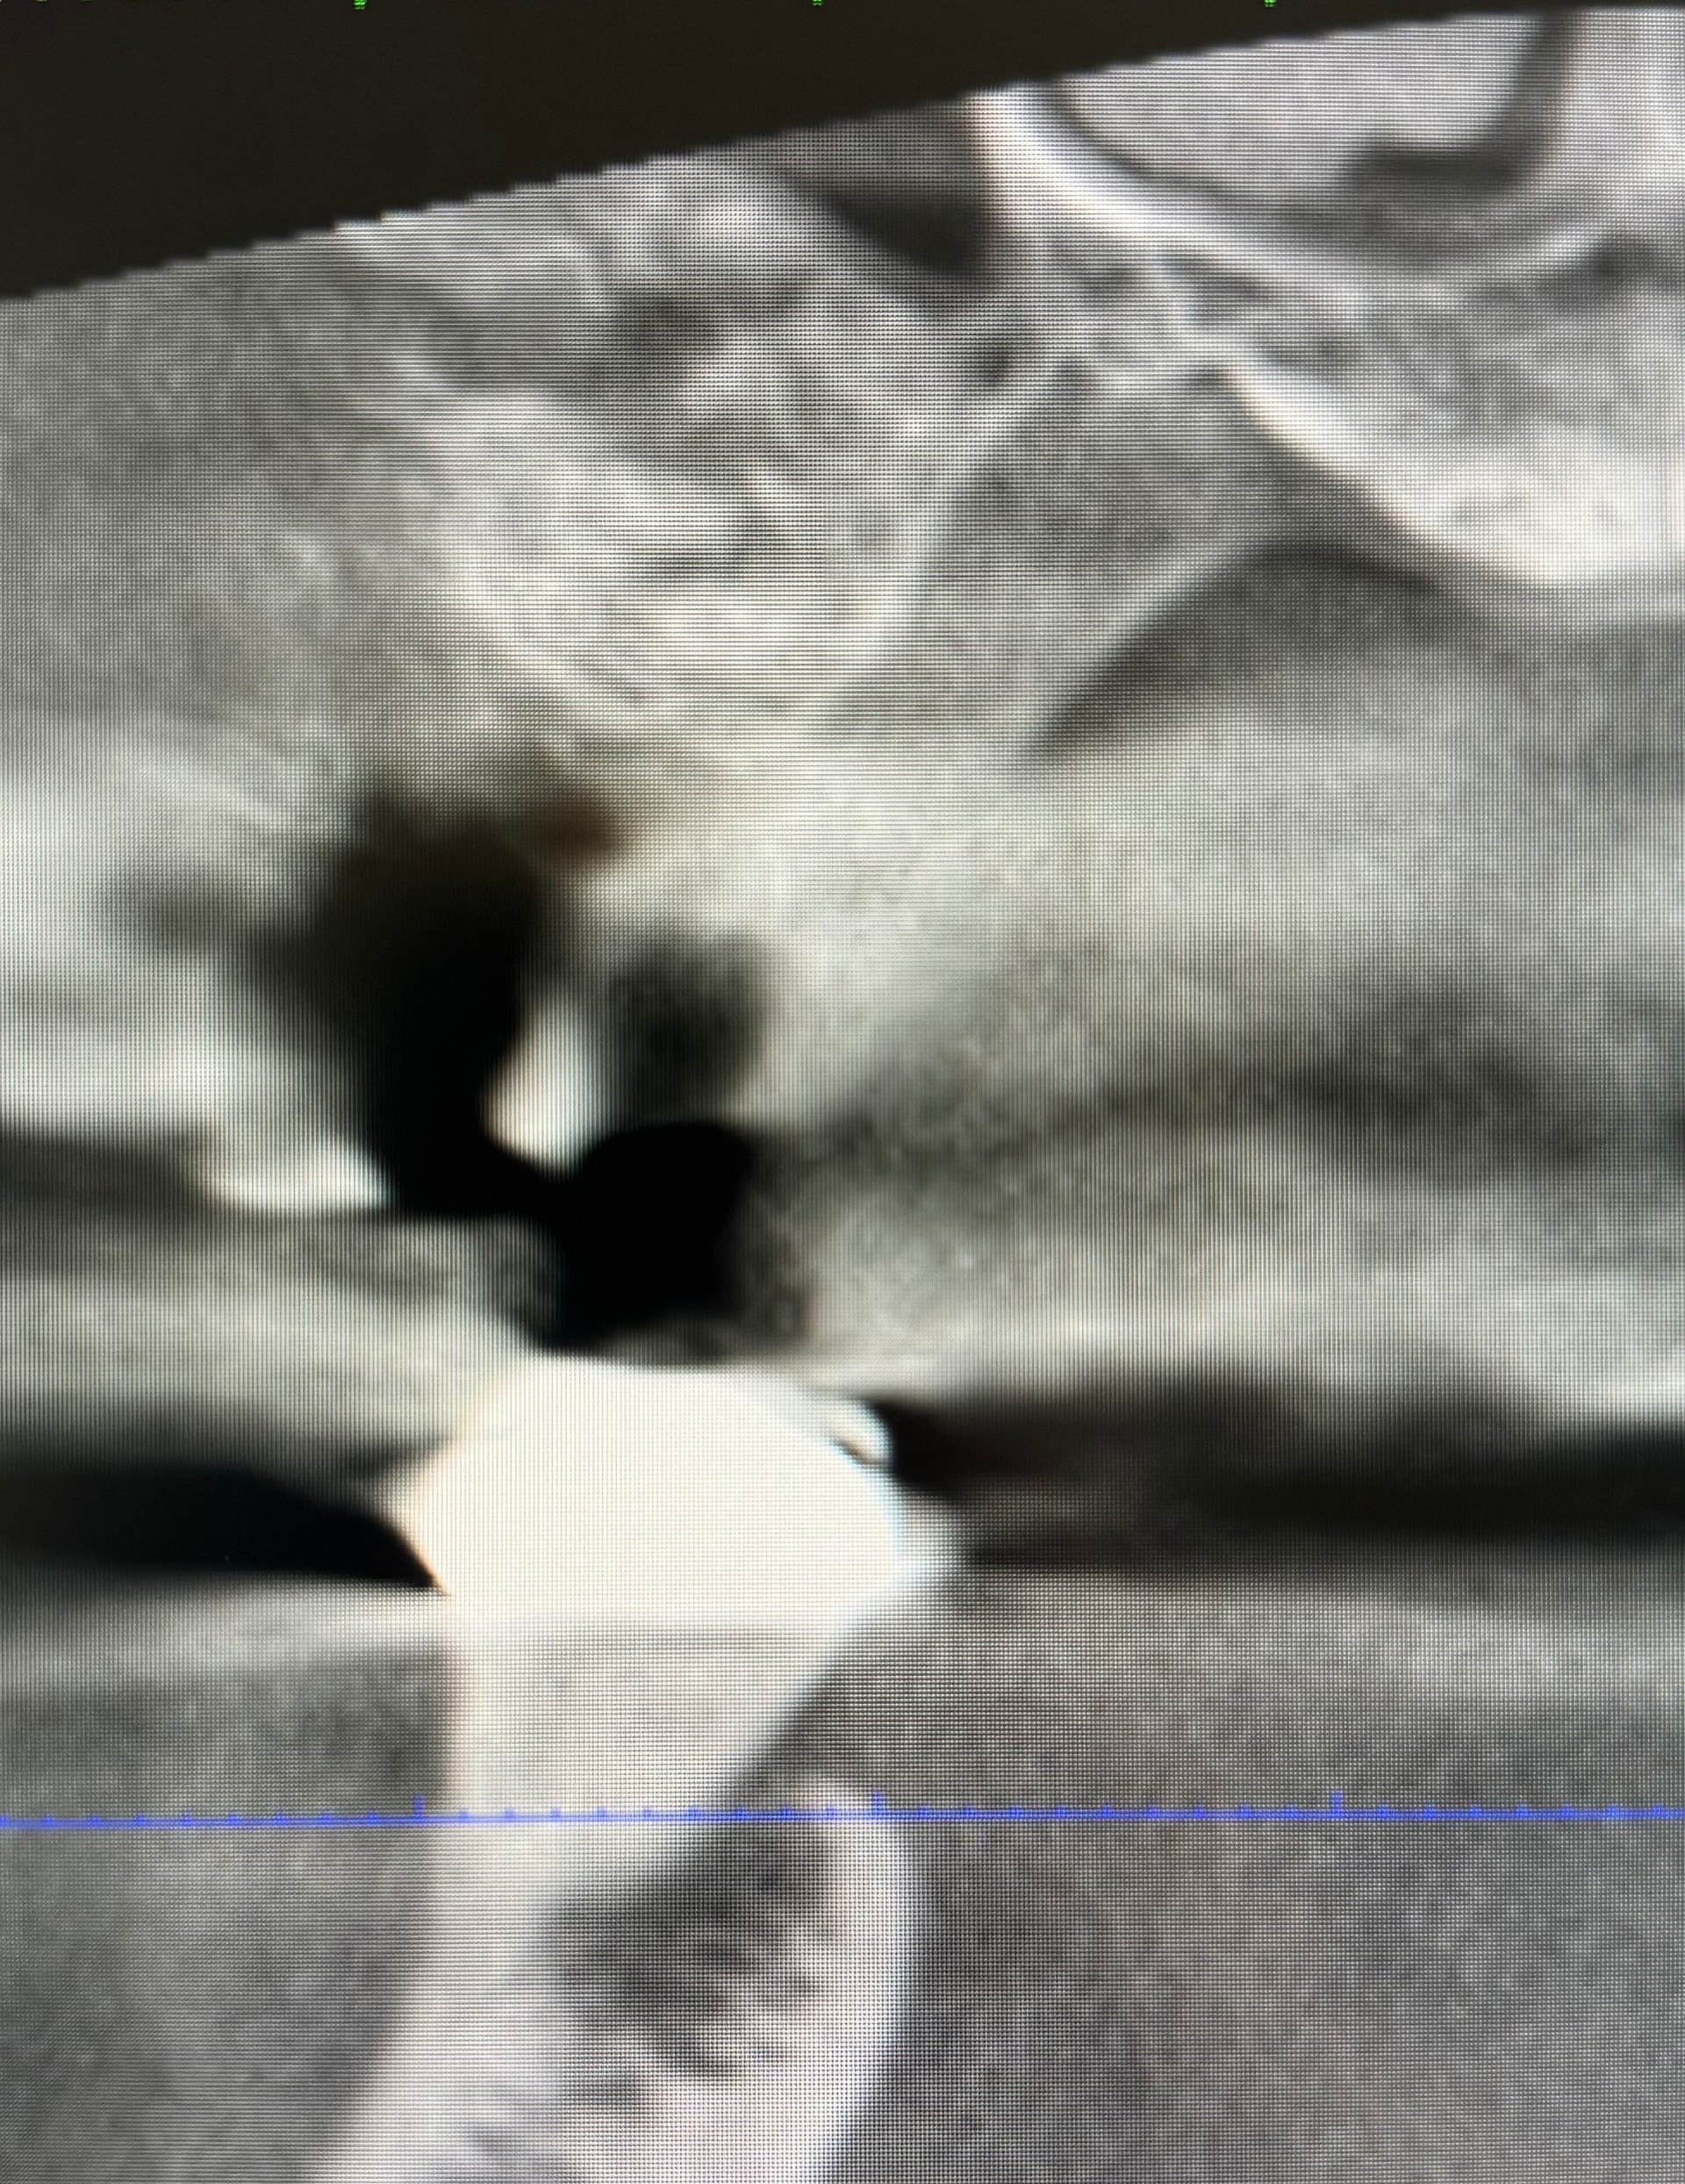

Specialist did a sinus lift in right maxilla. Is the void from the lateral window a concern? Would you bone graft at the apex at the time of implant placement?

the void might be a problem if your most of your implant is in the void.

that’s a strange artifact at on the CT. you got more slices of CT to upload?

if you want to graft at apex of implant. are you talking about doing a vertical sinus lift at the time of implant placement? that can be done. but it’s not exactly a space on the lateral. i do see bone on the medial of the sinus. but the lateral is not space (black) but gray which is either soft tissue or fluid. how this is your sinus floor? did you measure? and what length implant you are placing?

How long ago was the sinus lift and was it done with demineralized graft?? Demin will show up cloudy or as a void for 4-6 months post placement